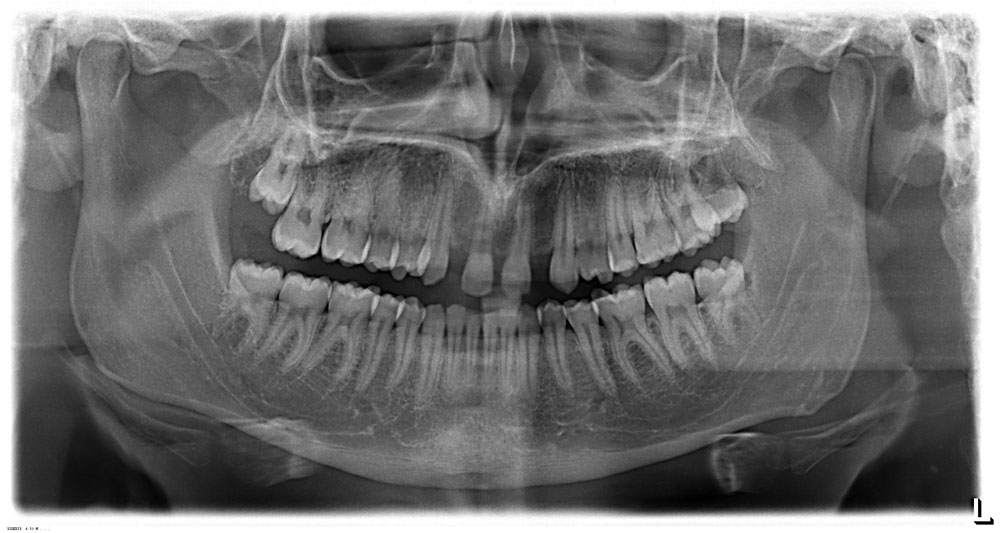

Le agenesie dentarie si diagnosticano generalmente durante gli esami radiografici di controllo effettuati nell’adolescente.

L’Ortodontista può sospettare la presenza di agenesie in caso di mancanza di eruzione di uno o più denti da latte oppure in presenza di un elemento deciduo che permane in arcata per più di sei mesi dalla perdita del corrispettivo dente da latte controlaterale.

In genere le agenesie dentarie si manifestano con presenza di spazi interdentali.